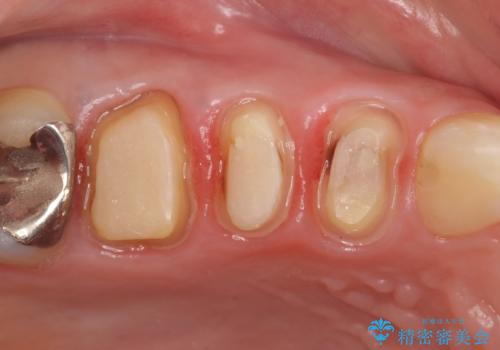

検査の結果右上5の歯の神経が死んでいたため、根管治療を行った後に、オールセラミッククラウンによる補綴を行いました。

また右上6に関しては再根管治療を行い、右上4に関しては虫歯治療を行った後に、オールセラミッククラウンによる補綴を行いました。

今回用いたオールセラミッククラウンはジルコニアフレームという白い素材の上にセラミックを盛っているため、審美性が非常に高いのが特徴です。